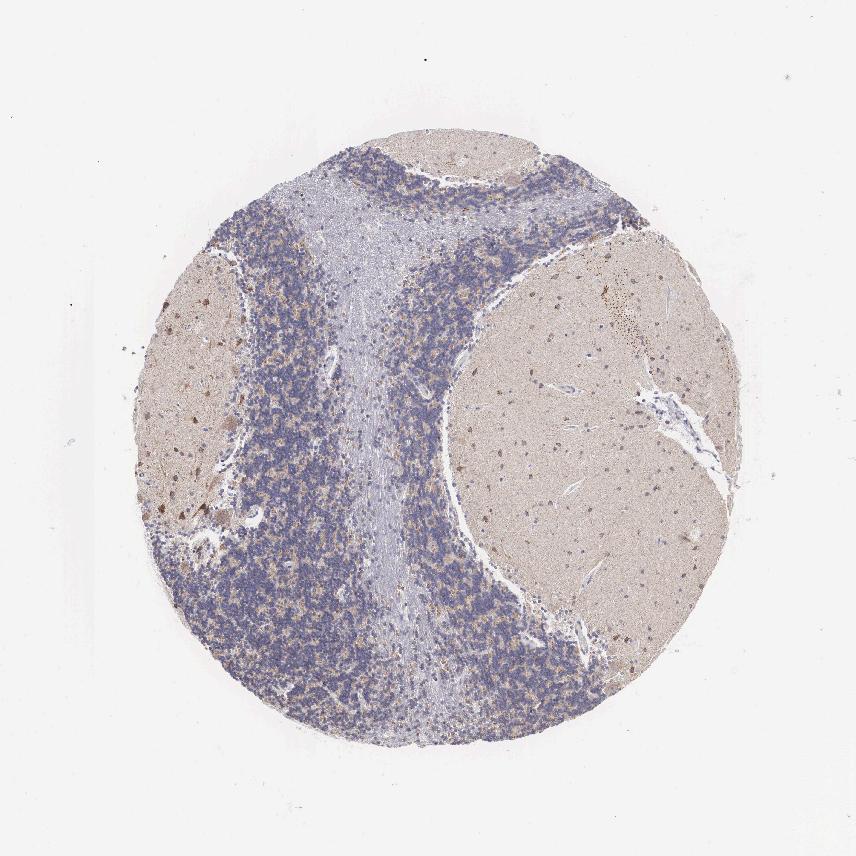

CEREBELLUM - Antibody stainingi

Antibody staining in the annotated cell types in the current human tissue is reported as not detected, low, medium, or high, based on conventional immunohistochemistry profiling in selected tissues. This score is based on the combination of the staining intensity and fraction of stained cells.

Each image is clickable and will lead to virtual microscopy that enables deeper exploration of all samples and also displays staining intensity scores, fraction scores and subcellular localization as well as patient and tissue information for each sample.

Antibody HPA000536Antibody CAB056152Antibody CAB056153

Purkinje cells MediumNot detectedNot detected

Cells in granular layer Not detectedNot detectedNot detected

Cells in molecular layer MediumNot detectedNot detected